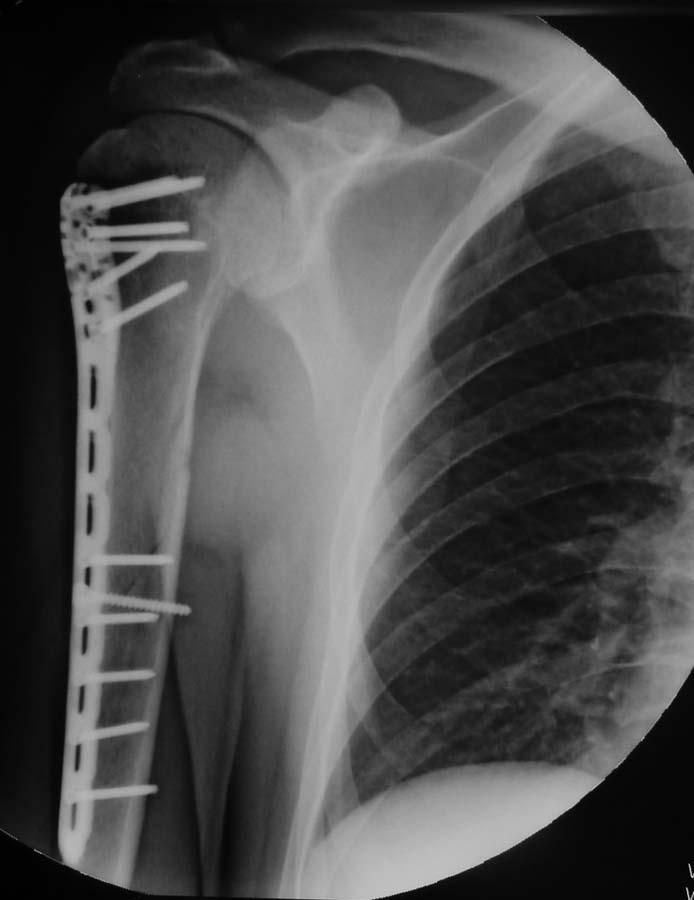

Сочетание перелома диафиза и головки плеча - рентгеноконтроль

Снимки через 41 день после операции: консолидация по типу первичной.

Длина пластины достаточна, размещение правильное. Поздравляю с отличным результатом!

Я согласен, что пластина короткая. Была достигнута идеальная репозиция и интерфрагментарная компрессия, но пластина дистально покрывает всего на два шурупа. Принцип АО о нейтрализации говорит, что после межфрагментарной компрессии можно минимизировать фиксацию. Можно на периферии по два шурупа, но более длинной пластиной, потому что в верхнем поясе другой механизм балансов сил. Кроме сгибания и разгибания, происходит ротация в плечевом поясе, и все необходимо нейтрализировать. Здесь также мощный дельтоид против длины конечности. Силы имеют тенденцию к варусной деформации, которые можно удержать только длинной пластиной, распределением сил по длине.